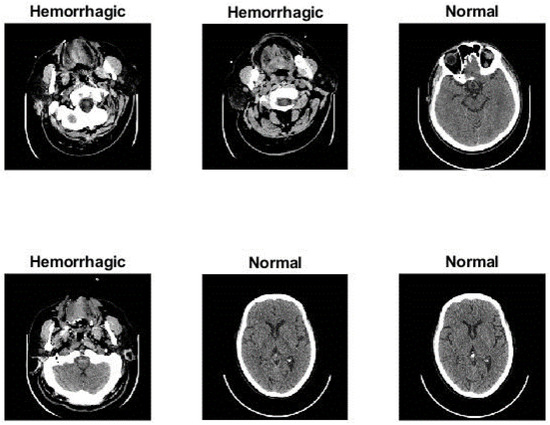

3.1. Description of the Dataset